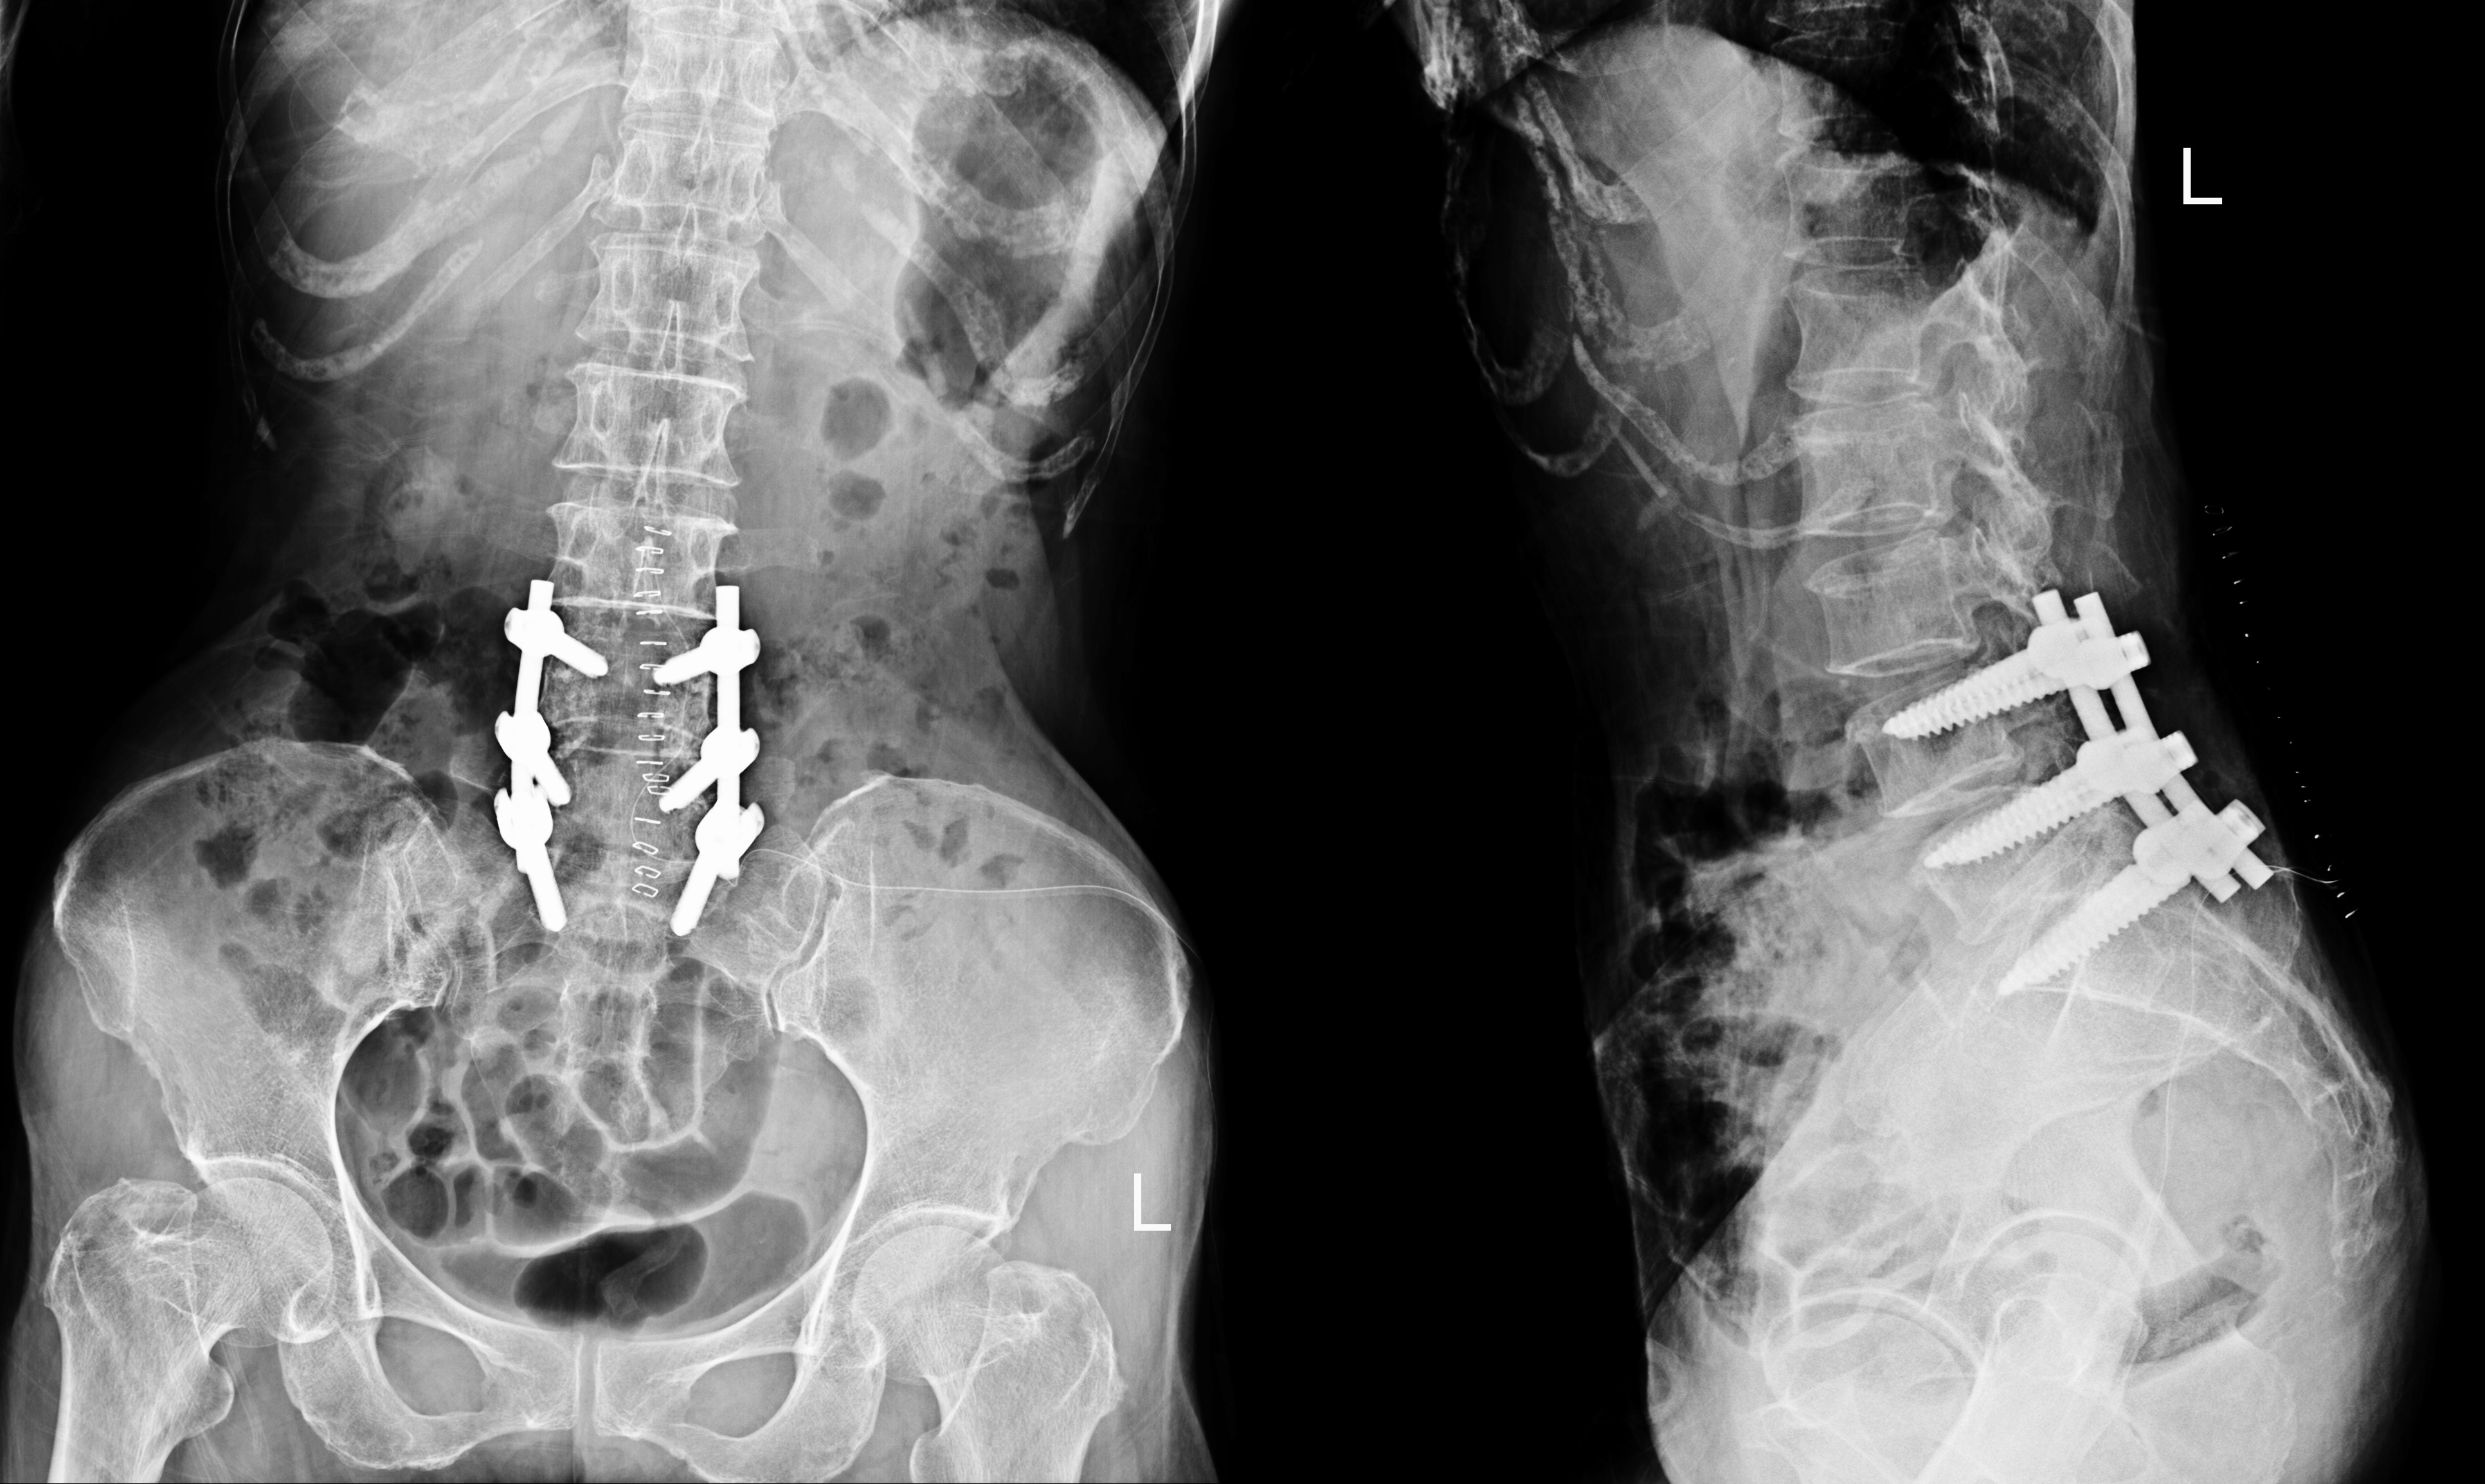

In extreme cases, think about how exercise may affect a person’s spine after a surgery that involves placing screws in their low back. Image Licensed from “rattanachot2525@gmail.com/depositphotos.com”